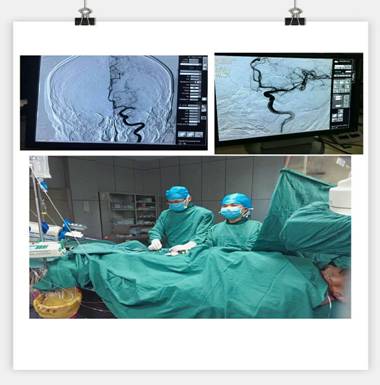

我院神經內科成功實施急性腦梗死靜脈溶栓聯(lián)合血管內介入治療的橋接搶救

凌晨3點30分, “叮叮?!币魂嚰贝俚碾娫掜戔彺蚱屏松钜沟膶庫o。 “你好,這里是急診科,請準備一張男床,腦血管意外患者”?;颊呤且幻?3歲男性,突發(fā)右側肢體乏力5.5小時,由家屬用輪椅推送入院。入科后患者神志昏睡,心率48次/分,血壓186/100mmHg,NIHSS評分20分。病人情況十分危急,在劉禮泉主任指示下,患者為急性缺血性卒中,有溶栓指征。在劉主任與家屬談話期間,值班醫(yī)生同時開出醫(yī)囑,患者予以硝普鈉控制血壓+尿激酶靜脈溶栓。夜班護士立即給病人抽血、吸氧、心電監(jiān)護、建立靜脈通道、準備藥物……我們忙而不亂,默契配合。溶栓過程中劉主任一直守護在病人身旁,隨時觀察病人的病情變化。溶栓后,患者右側肢體有自主活動,但乏力癥狀及意識障礙無明顯緩解,劉主任立即決定行頭頸聯(lián)合CTA,明確是否有大血管閉塞。果不其然,患者頭部CTA提示左側大腦中動脈M1段栓塞,如果大血管得不到及時開通,必然會出現(xiàn)災難性的后果。劉主任建議家屬考慮是否行血管內治療開通血管,經過耐心細致的溝通,患者家屬同意行急診腦血管造影檢查及血管內治療。 同時立即召集曾比賢副主任、聶利珞副主任趕來醫(yī)院,為患者在局麻下行全腦血管造影+顱內血管取栓術。時間伴隨著沉悶緊張的氣氛一分一秒地過去,取栓的生命通道終于打開,患者病變血管恢復良好,手術圓滿成功,此時灰暗的天才微微光亮……

在急性腦梗死患者緊急救治中,時間就是生命,該病例運用了動靜脈聯(lián)合的方式治療急性腦梗塞,有效地保護了患者的大腦,此類技術在國內處于領先治療手段,溶栓、取栓同步進行的橋接搶救措施起到了至關重要的作用。該病例成功取栓意味著我院神經內科在治療急性腦血管病方面已經從傳統(tǒng)的靜脈溶栓向介入取栓的現(xiàn)代化治療方式轉變。